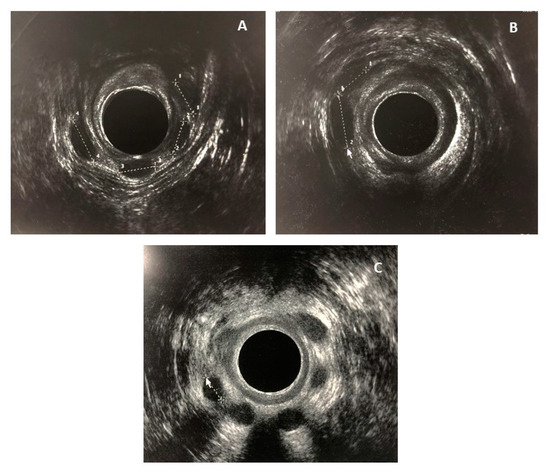

| Endoanal US § | |

| No lesion | 9 (69%) |

| IAS ¶ lesion ‡‡ | 3 (23%) |

| IAS & EAS †† lesion §§ | 1 (8%) |